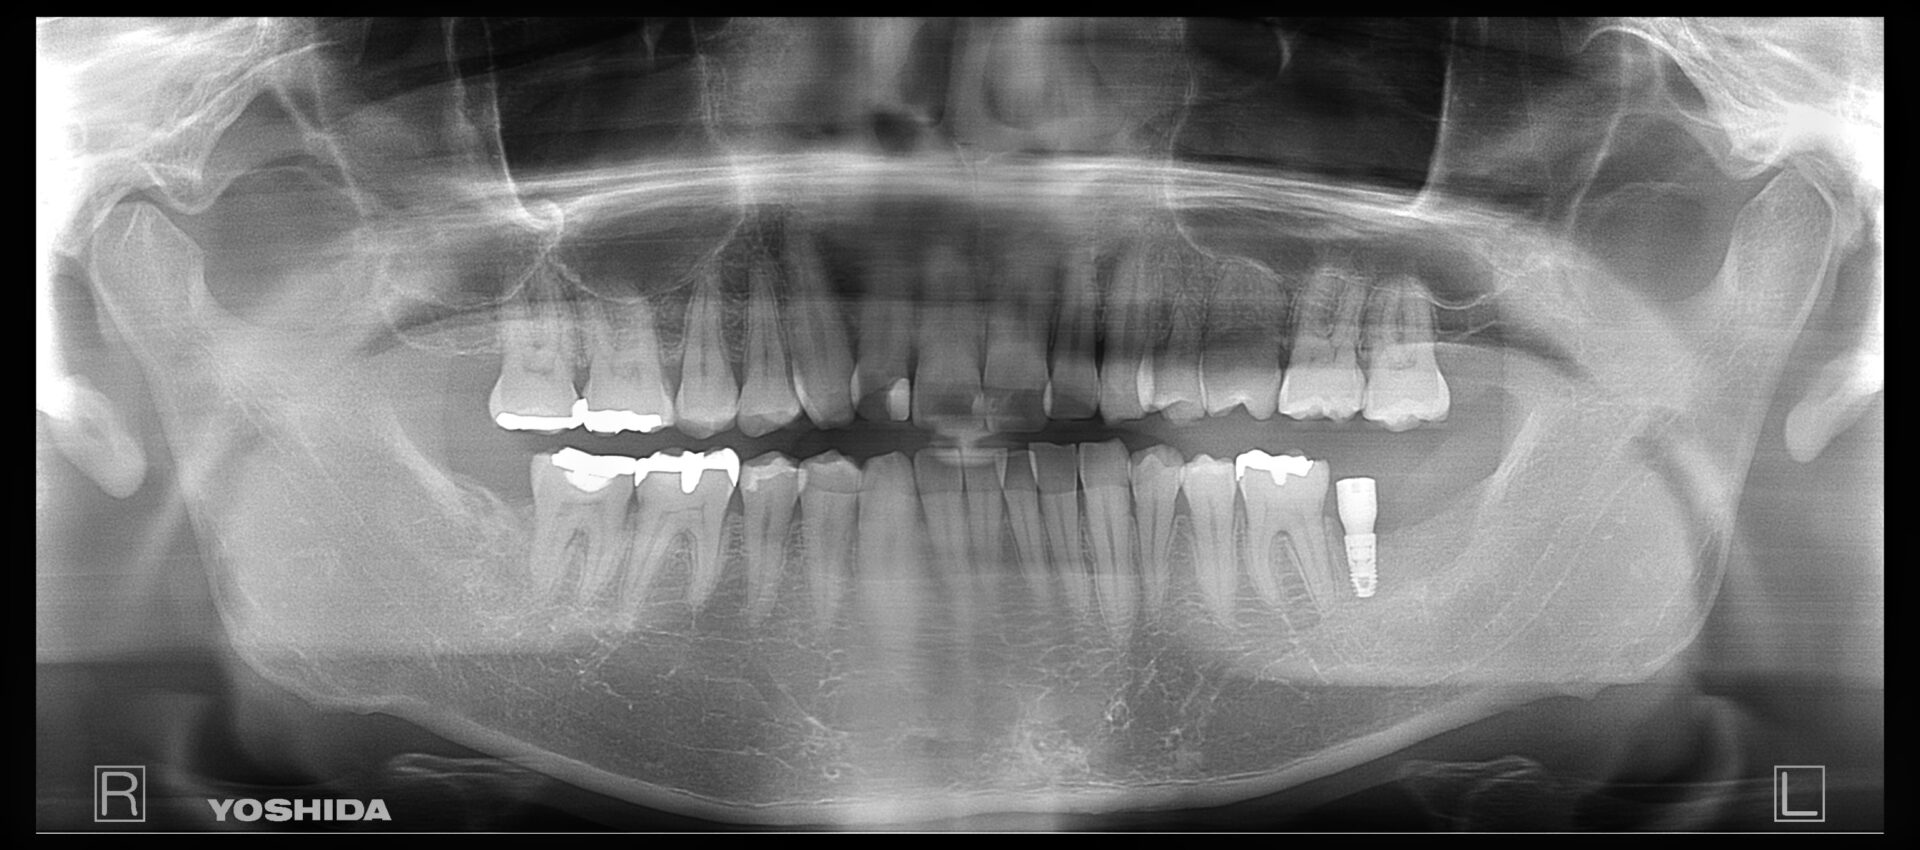

50代女性

右上4,5番インプラント術前

インプラント術後(1年経過)

費用 | 800000円 |

治療期間 | 9ヶ月 |